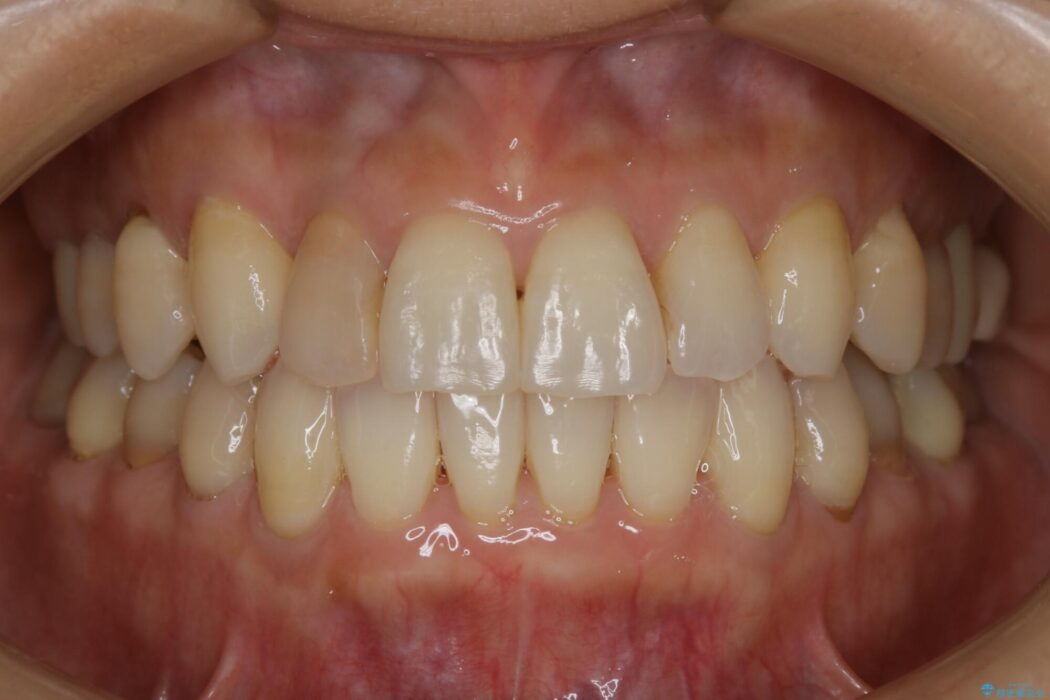

治療後について

気になっていたガタつきも改善され、患者様にはご満足いただけました。